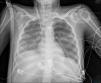

A 19-year-old woman, with a past medical history of Steinert's myotonic dystrophy, intubated due to severe respiratory distress after an exploratory laparotomy for intestinal pseudo-obstruction. In tracheal aspirate, Escherichia coli without resistance mechanisms. Very poor pulmonary mechanics (compliance < 2 mL/cmH2O) and no response to prone positioning, veno-venous ECMO is cannulated, and given the high airway pressures with 4 mL/kg of ideal body weight, ventilation is switched to airway pressure release ventilation (APRV): high pressure 15 cmH2O; high time 6 s; low time 0.3 s. Initially 10 mL of exhaled volume. Radiographic progression is shown in the images (Fig. 1: day 0; Fig. 2: day 2; Fig. 3: day 5). This case is an example of how APRV ventilation while ensuring gas exchange with ECMO can be useful in the management of patients with refractory respiratory distress.